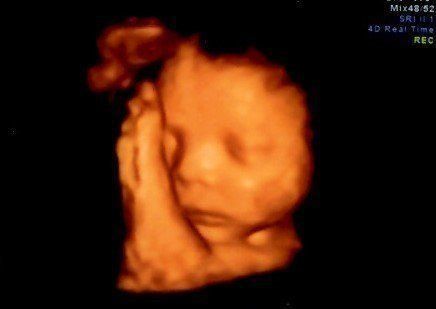

妊娠28週目のエコー写真 3D画像を撮影することを決意

健診を受けていた病院からもらうエコー画像は、ごく一般的な2Dタイプ。私は、この時期だけの赤ちゃんの姿を記念に残したかったことと、赤ちゃんが本当に元気に育っているのかをはっきりと確認したかったので、3D画像の撮影だけでも予約可能な産院を探すことを決意。この時すでに赤ちゃんがこれ以上大きくなると映りにくくなるというぎりぎりのタイミングでした。

妊娠29週目のエコー写真 3Dのエコー画像撮影にチャレンジ

わざわざ別の産院に出向き、高い料金を払って3D画像撮影に挑んだものの、なんと、撮影した時間帯の赤ちゃんはおなかに向かって後ろ向きにおねんね中。残念ながら期待していたような顔がわかる3D画像は撮影できませんでした。それでも、2D画像ではわからなかった腕や後ろ姿が鮮明に写っており、とても興奮しました。

妊娠31週目のエコー写真 3Dエコー画像撮影に再チャレンジ

以前の3D画像撮影で赤ちゃんの顔の撮影ができなかったことがどうしても心残りで、義理の母が上京するタイミングに合わせて再撮影にチャレンジ。病院からは、この時期は赤ちゃんが育ちすぎているので希望通りに撮影できるかわかりません、と言われていました。それでも撮影中は、看護師さんが寝ている赤ちゃんをおなかの上から優しくゆすって顔の位置を変えてくれ、無事撮影することができました。

入院後は次々と襲ってくる激しい陣痛に10時間以上耐えました。そして何度も検査した結果、医師の判断で帝王切開をすることが決定。夫は看護師に促されるままに同意書にサインし、私は即手術台へ。あっという間に4100g、54cmのビッグサイズのわが子が、妊娠40週と5日目に誕生しました。初めて見たわが子の顔は、3Dエコー画像で見たものとそっくり。夫婦で笑ってしまいました。